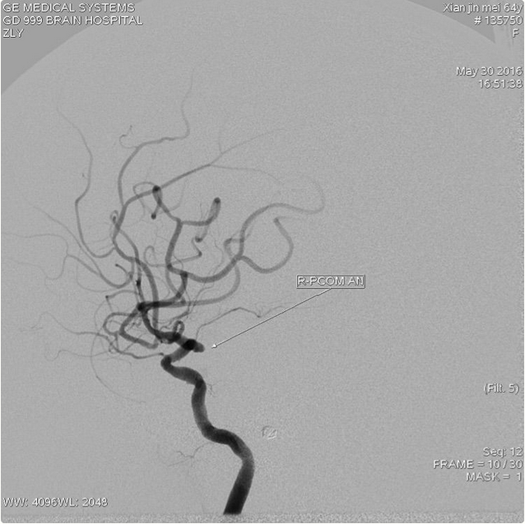

右侧颈内动脉造影:右侧后交通动脉瘤,大小约2.0×2.5mm;